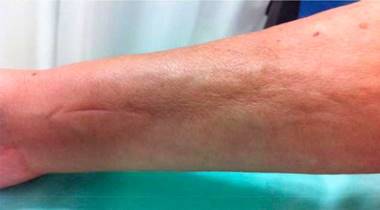

Physical examination showed livedo reticularis in the lower limbs (Fig. 1), as well as induration, which affected the inner side of the thighs, lower hemiabdomen, and upper limbs, being the right upper limb the site where it appeared with the highest intensity with “orange peel skin” changes (Fig. 2) and a longitudinal depression in the ventral surface (Fig. 3) but without affecting the region of the skin distal to the wrist.

Within the clinical manifestations, patients begin with weight loss (26%), asthenia (38%), and myalgias (67%).27 90% of patients have skin involvement and up to 60-80% of patients have muscle and joint involvement.1 The most frequent locations of EF are the upper limbs in 88% followed by the lower limbs in 70%, and, to a lesser extent, involvement of the trunk and the neck with 32 and 18%, respectively. 1,2,4 This cutaneous affection begins with erythema, edema, and thickening of the skin of the extremities, symmetrically, although it has been reported unilaterally. 28 The commitment of the extremities usually respects the most distal region; however, in some cases, especially in those related to bone marrow transplantation, it can be found pitting edema29 in hands or fingers. 30 Subsequent to these changes, "orange peel" changes appear and finally there is a marked induration. This phenomenon can become so intense that compartmental syndromes derived from the disease have been described. 31 The coexistence of morphea-type lesions has been reported32 in up to a third of patients and they should be considered part of the disease. 1,4 The groove sign, which consists in a depression that is formed in the traject of the superficial veins in the distal region of the extremities and is best observed when they are elevated, is pathognomonic of this pathology. It is caused by the separation of the superficial dermis and the epidermis, secondary to the fibrotic process. 33,34